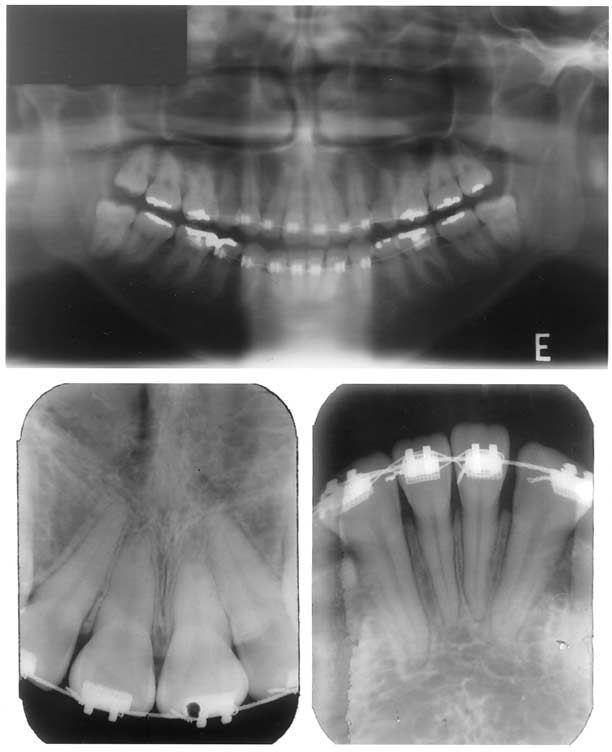

Fig 5. Panoramic and periapical radiographs before retreatment, with old appliances still in place.

A 23-year-old woman came for orthodontic treatment to the private orthodontic office of Dr M.R.J. Her major complaint was the persisting large overjet. She was undergoing orthodontic treatment with extraction of 4 first premolars to correct a Class II Division 1 malocclusion. Unfortunately, her treatment was not proceeding well because of her lack of compliance with headgear to reinforce anchorage. As a result, despite the extractions, she still had a significant overjet (Figs 1-3). There was no crowding, and the curve of Spee was mild. Because she was not satisfied with her progress at that stage, she abandoned treatment, with the orthodontic appliances still in place. One and a half years later, she decided to continue her treatment with Dr M.R.J. Cephalometrically, there was a severe Class II skeletal relationship with compensating maxillary and mandibular incisor tipping. The soft tissue profile was convex with a retruded mandible and chin (Fig 4 and Table). However, the patient said nothing about these characteristics. Radiographically, the maxillary third molars were in a favorable position functionally, but the mandibular third molars were not. Because of the previous unsuccessful orthodontic treatment, the maxillary incisors already had significant root resorption (Fig 5). There were no signs of active periodontal disease.

On the other hand, conditions that could have contraindicated this treatment approach would be severe resorption of the incisors caused by the previous orthodontic treatment attempt, potential root resorption, temporomandibular joint symptoms, or active periodontal disease. Although her maxillary incisors exhibited greater root resorption than usual, we did not consider this factor to be a contraindication for treatment if we used light forces and evaluated progress with periapical radiographs. Additionally, she did not exhibit potential local factors for root resorption. 24-26